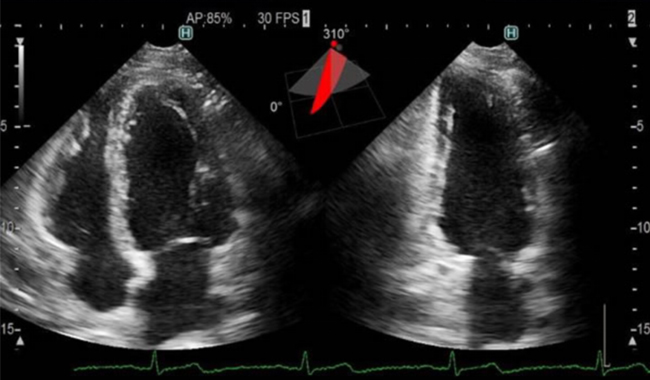

心エコー検査は、心臓に超音波を当て、跳ね返ってくるエコー(反射波)を画像に描出する検査です。

これによって心臓の大きさや動き、弁の状態などを観察できるので、心筋梗塞や心臓肥大、弁膜症などの疾患を調べるときに行われます。